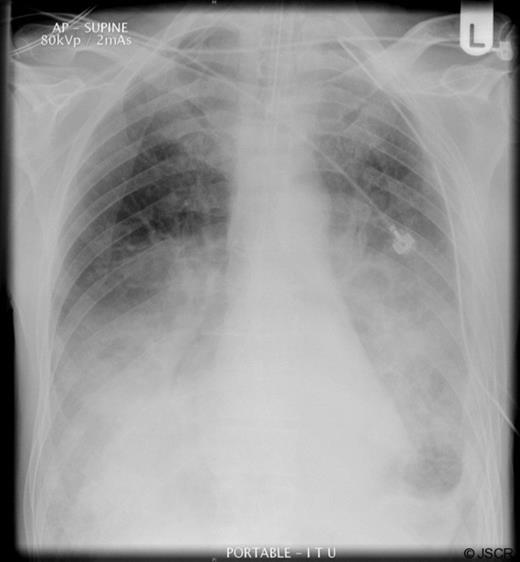

A clinical diagnosis of a possible spontaneous rupture of the diaphragm was made. The patient underwent an emergency laparotomy as he was not stable enough to undergo cross-sectional imaging to confirm the diagnosis. There were no abnormal findings at laparotomy. A left sided chest drain was immediately inserted with release of air under tension and pus (Figure 2).

The patient remained intubated for five days, initially being weaned onto CPAP, and spent ten days in total on the intensive care unit. He developed a small residual empyema on the left side after the chest drain was removed which resolved with an extended course of antibiotics. He spent a total of 6 weeks in hospital before discharge with support at home. At a follow up outpatient appointment two months he remained well.